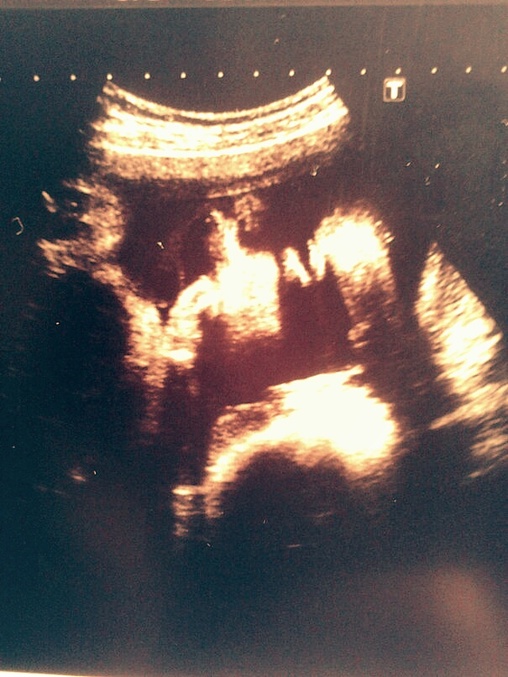

И наконец-то фото наших щечек, вернее левой стороны личика, правая в темноте:-)

Счастья полные штаны. Я так рада была видеть свою красавицу:-) Напишу сейчас много букв с протокола, чтоб потом не забыть:-) Доча все время толкала датчик, но дядя доктор ее все равно со всех сторон измерял. Еще она сладко плямкала и нам врач показал какие у нас на затылке волосики выросли:-)